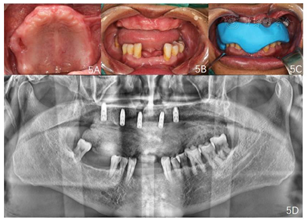

患者,男性,59岁,工程师,因近年来多颗牙齿陆续自动脱落,于2020年5月来我院种植科就诊。牙科既往史:修复史。全身健康状况:否认全身系统性疾病及药物过敏史。家族史:否认遗传性疾病史。无不良生活嗜好,不抽烟。

口外检查:颌面部左右大致对称,双侧颞下颌关节检查未见异常。

口内检查:上颌大部分牙齿缺失,余留13、16牙周红肿,牙龈退缩,牙根暴露,13松动Ⅲ度,16松动Ⅱ度;缺牙区牙槽嵴低平,上颌弓窄小,上颌正中腭侧可见一小米粒大小脓包,探诊有黄白色脓液溢出。下颌31、32、41缺失,42Ⅲ度松动,46、47缺失,缺牙区牙槽嵴低平;38、48垂直正位萌出,38颊

面大面积牙体组织龋坏,黑色腐质达牙本质深层;48

面窝沟呈黑色改变,探诊质软,达牙本质层,38、48牙龈退缩,根分叉暴露。口腔卫生差,下颌余留牙舌侧牙颈部连续牙结石堆积,牙间隙内附着大量黑色结石,下前牙牙龈退缩2~4 mm;无稳定咬合关系。

牙周专科检查示74%的位点PD≥3 mm,BOP为73%,牙龈呈暗红色,质脆,轻探出血。(图1)